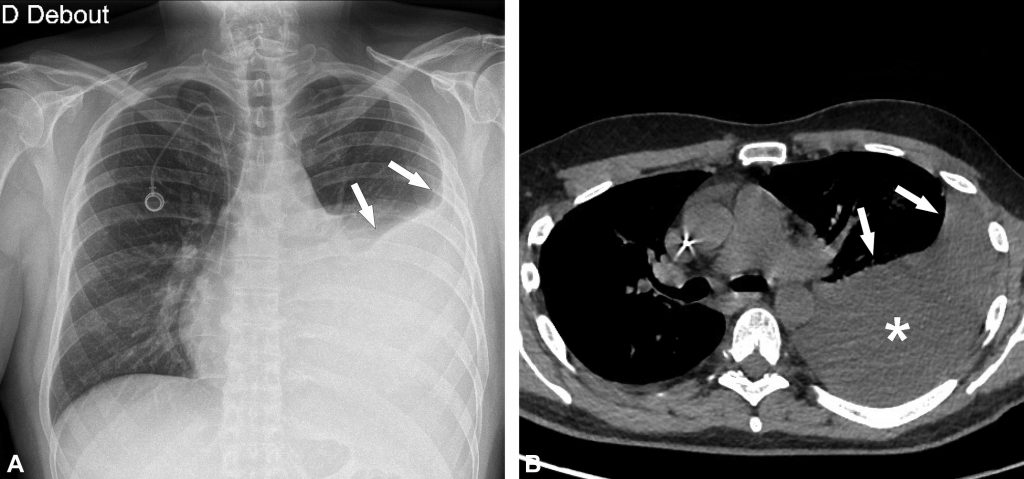

Fig. 91.3. Radiographie de face debout d’un hydropneumothorax droit.

La limite supérieure de l’épanchement liquidien droit est horizontale (flèches), ce qui suggère un niveau hydroaérique. Le niveau hydroaérique est confirmé par la présence d’un pneumothorax droit associé (têtes de flèches).

Source : CERF, CNEBMN, 2022.

En cas d’épanchement de faible abondance, on peut n’observer qu’un effacement d’un récessus (ou cul-de-sac) costodiaphragmatique (figure 91.4), visible plus précocement sur le cliché de profil.

Fig. 91.4. Radiographies thoraciques et scanner d’un épanchement pleural gauche de faible abondance.

L’épanchement gauche n’est pas visible sur l’incidence de face (A), alors qu’il est bien visible sur l’incidence de profil qui est plus sensible pour les épanchements de faible abondance (flèche en B). Le scanner chez le même patient montre l’épanchement pleural gauche de faible abondance en situation postérieure (flèche en B).